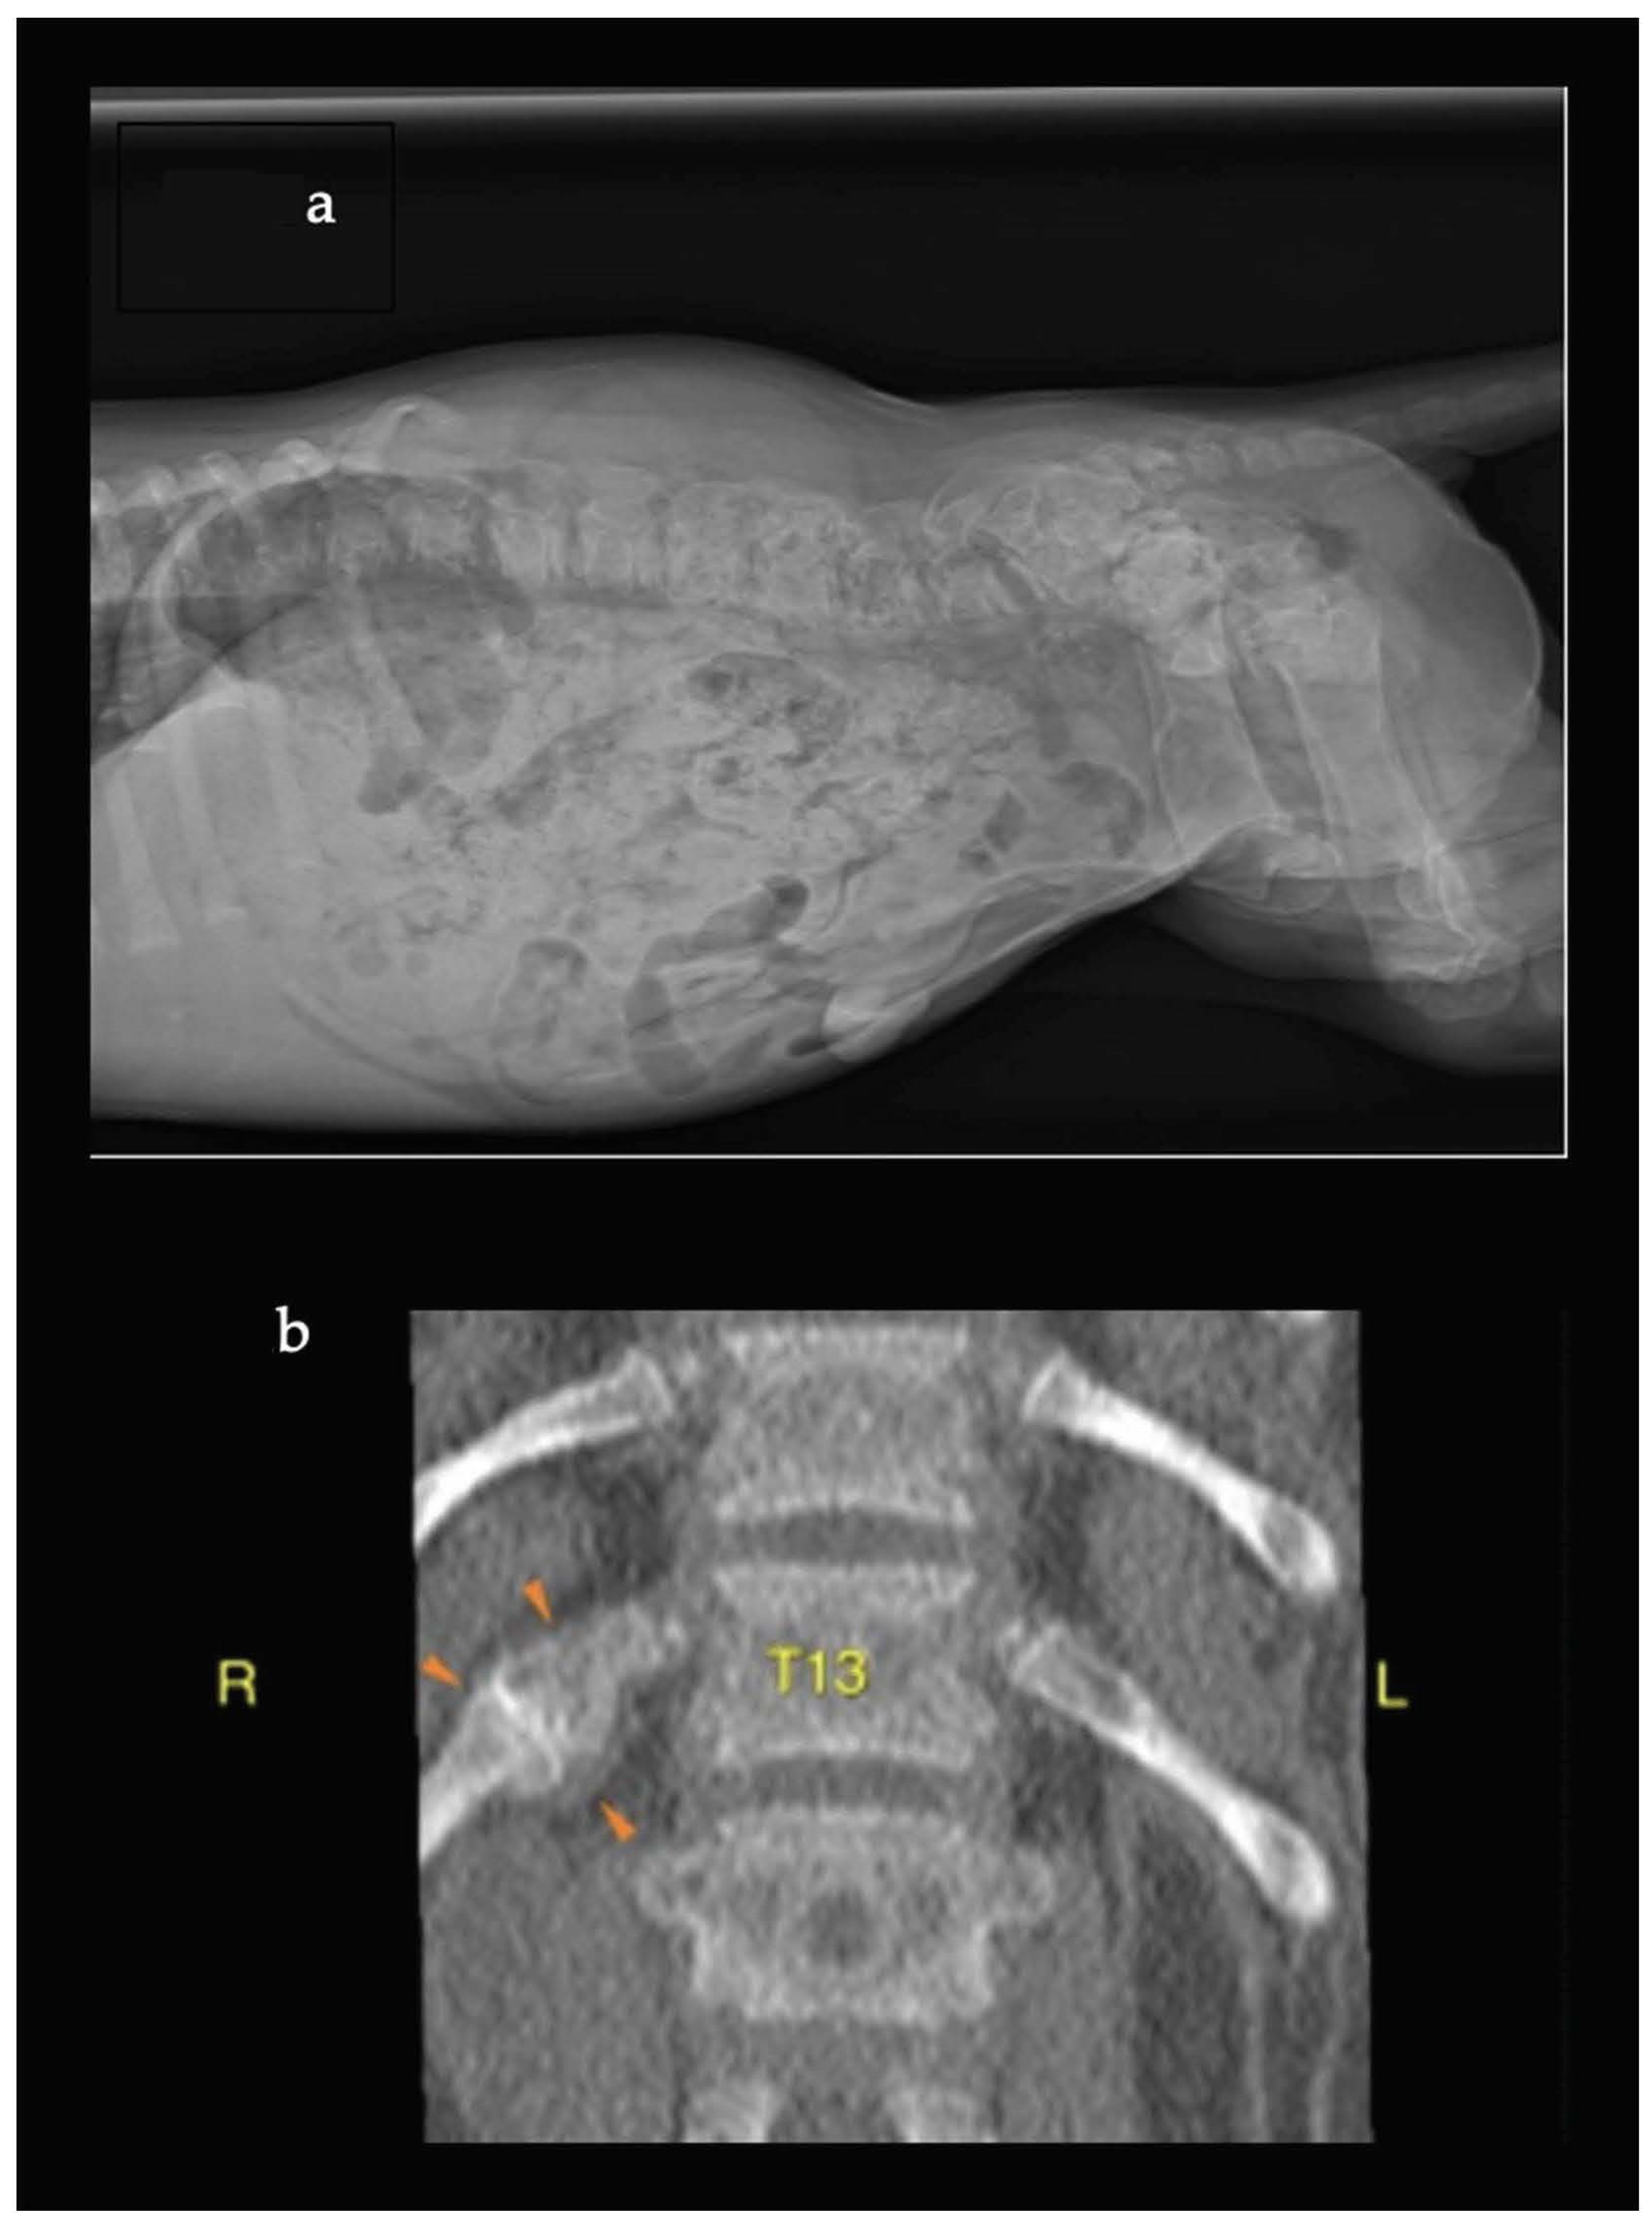

2. Case Descriptions

3. Diagnostic Work-Up, Therapeutic Intervention, and Outcome